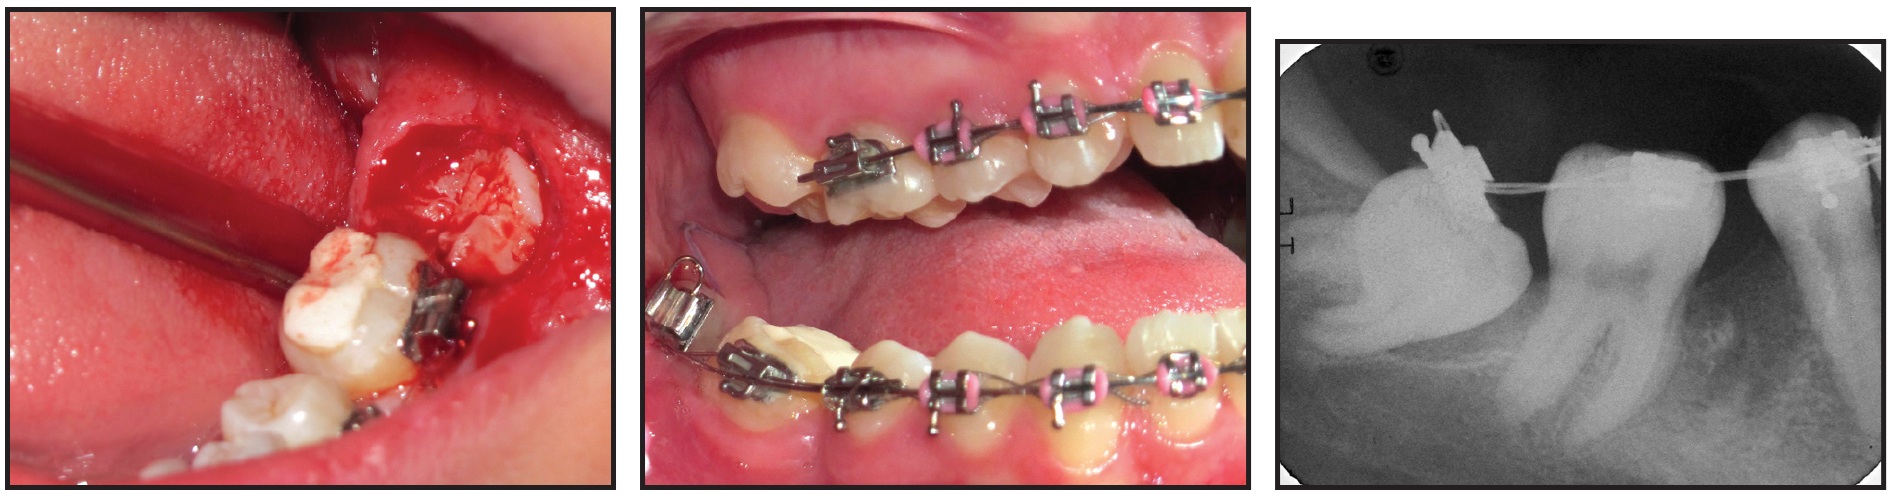

After three months of treatment, the patient was referred for surgical removal of the impacted upper canines and extraction of the lower right first molar. Lacebacks were added with ligature wire in the lower buccal segments to help relieve the crowding (Fig. 4).

Fig. 4 After surgical removal of impacted upper canines and extraction of lower right first molar, lacebacks added in lower buccal segments to help relieve crowding.